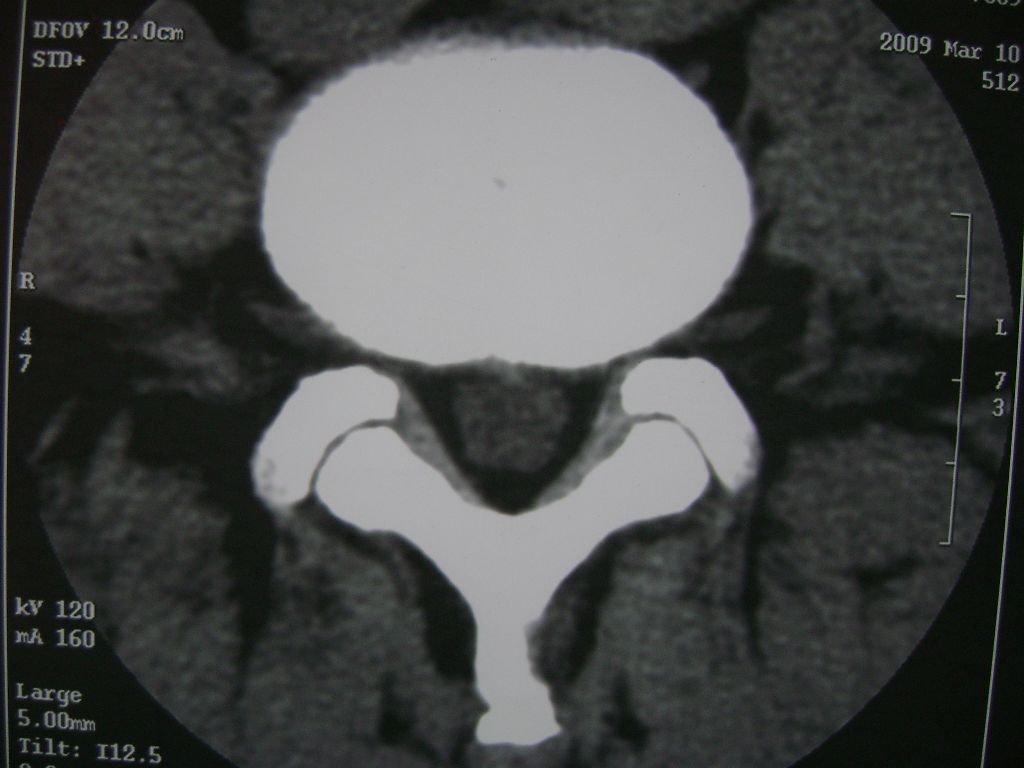

m  50  腰痛

两个椎盘均有膨出及突出改变,下一个尚有椎盘积气,后纵韧带钙化,另椎管脂肪过多症

椎间盘膨出,后纵韧带钙化,骨质增生

两个椎间盘中央型重度突出,黄韧带增厚。

两个椎间盘膨出并突出,下一个椎间盘变性;双侧黄韧带钙化。